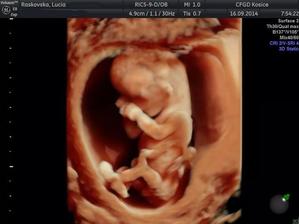

♥ 16.september prvotrimestrálny skriníng v 12tt (v Myslave) všetko v poriadku, odber krvi a máme prvé 3D fotky a na 80% potvrdené pohlavie 🙂